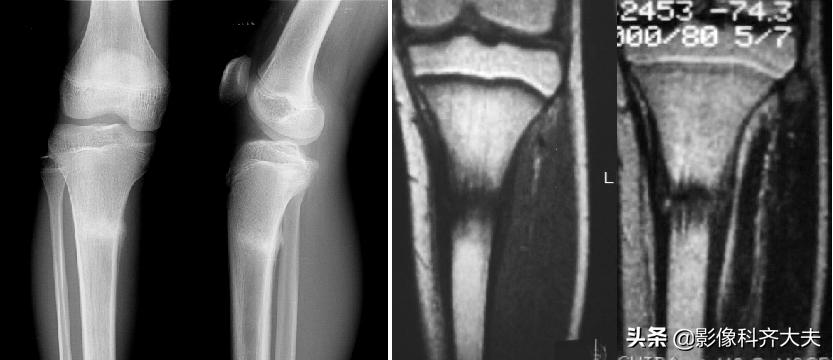

骨挫伤(bone bruise):外力作用引起的骨小梁断裂和骨髓水肿、出血,T1WI低信号,T2WI高信号,压脂序列显示清晰。平片和CT 上常无异常发现。

例:右胫骨骨挫伤

右胫骨骨挫伤-平片正常

右胫骨骨挫伤-CT正常

右胫骨骨挫伤-MRI清晰显示病灶位置

胫腓骨骨挫伤

胫腓骨对应性骨挫伤